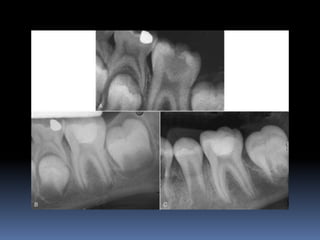

OPEN APEX  Anopen apex is the developing root of an immature tooth until apical closure occurs .  Apical closure occurs 2-3 yrs after tooth eruption  Any injury to the pulp at this stage will stop the closure of the apex  Such a tooth will have short , thin walls at the apical portion of the root

 Open apexcan also be caused by extensive resorption of a previously mature apex after orthodontic treatment or severe periapical inflammation

Diagnosis and assessment: History  Subjective symptoms  Diagnostic tests  Radio graphs A radiolucent area usually surrounds the apex of an immature root with a healthy pulp

OPEN APEX VITAL PULP APEXOGENESIS NONVITAL PULP APEXIFICATION

APEXOGENESIS A Vital Pulp Therapyprocedure performed to encourage continued physiologic development and formation of the root end. Since the main objective is to maintain the vitality of the radicular pulp the pulp must be vital and capable of repair